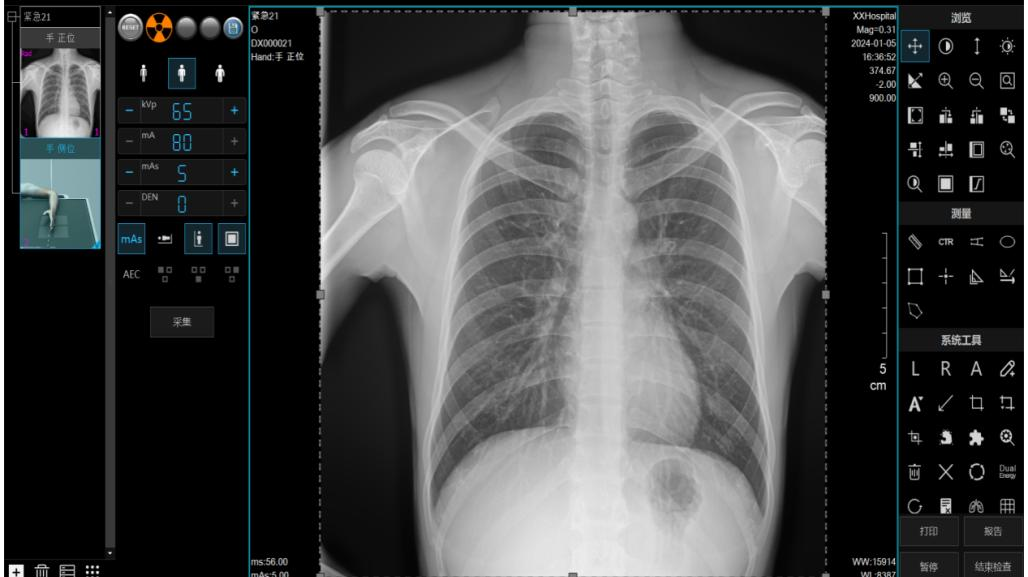

自适应图像重建算法:能智能识别拍摄部位,自动优化图像对比度与信噪比,确保在快速出图的同时,图像质量满足肺炎、骨折等公卫常见病的诊断需求,让筛查结果可靠、放心。